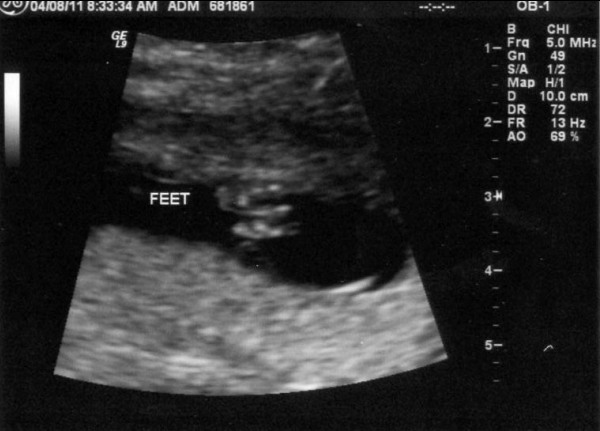

We had yet another ultrasound today. The baby's weight is estimated at 2 pounds 3 ounces which puts him in the 50th percentile for his gestational age -- right at average in other words. The sonographer made a comment about how she had to chase the baby around to get the measurements she wanted. It made me think... if she has to chase him around now, when he's in a very enclosed space, what does that imply about how much we'll have to chase him when he learns to crawl and walk?

Here is a hand with the fingers extended. We don't have a picture of it, but we also saw his other hand, which was clenched into a fist with his arm bent. It looked like he was getting ready to give me a good punch!

Here is a foot.